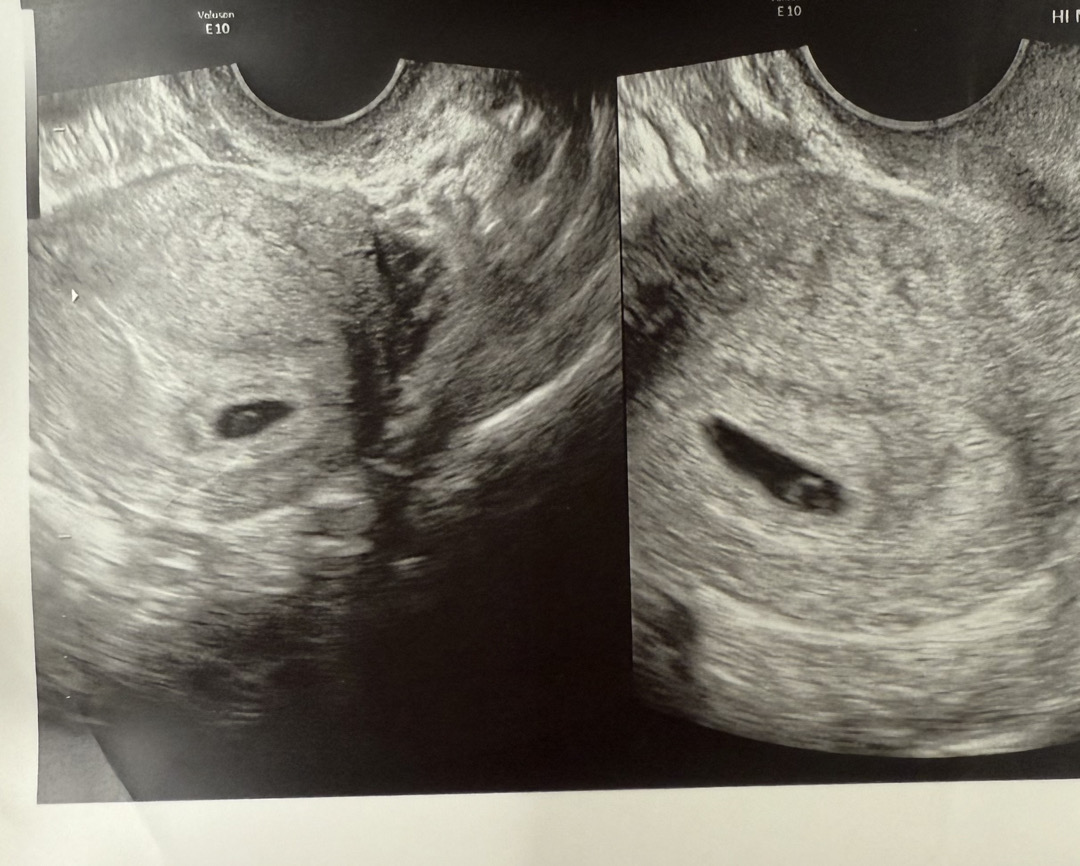

아기집이 이렇게 길쭉하기도 한가요..?

동그랗게 예쁜 모양이 아니어서 신경쓰여요 ㅋㅋㅋ 다리 뻗을 곳을 미리 준비하나 싶고 ㅋㅋ 이런 아기집 보신 분 있으신가요..?